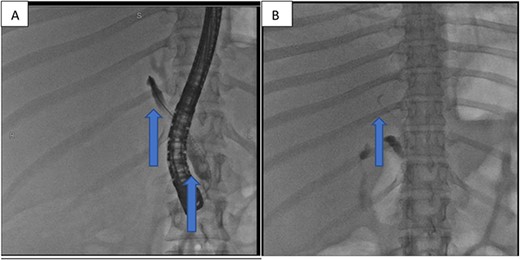

At our facility, ERCP was done. The bile duct was cannulated with 0.035 wire-guided sphincterotome. Cholangiogram showed normal caliber biliary tree with one filling defect in the distal CBD and contrast leak from duct of Luschka to the gall bladder bed (Fig. 1). There was no contrast leak from the cystic duct stump (Fig. 2A). Standard sphincterotomy was performed and a single mulberry stone was removed using stone retreival balloon and double pig tail biliary plastic stent was placed into the RHD and good bile flow was achieved post procedure (Fig. 2B).

Fluoroscopy image indicating bile leak from type 2 duct of Luschka.

(A) First fluoroscopic image shows evidence of no bile leak from cystic duct stump as indicated by the arrows; (B) second fluoroscopic image shows a stent placed into the RHD.